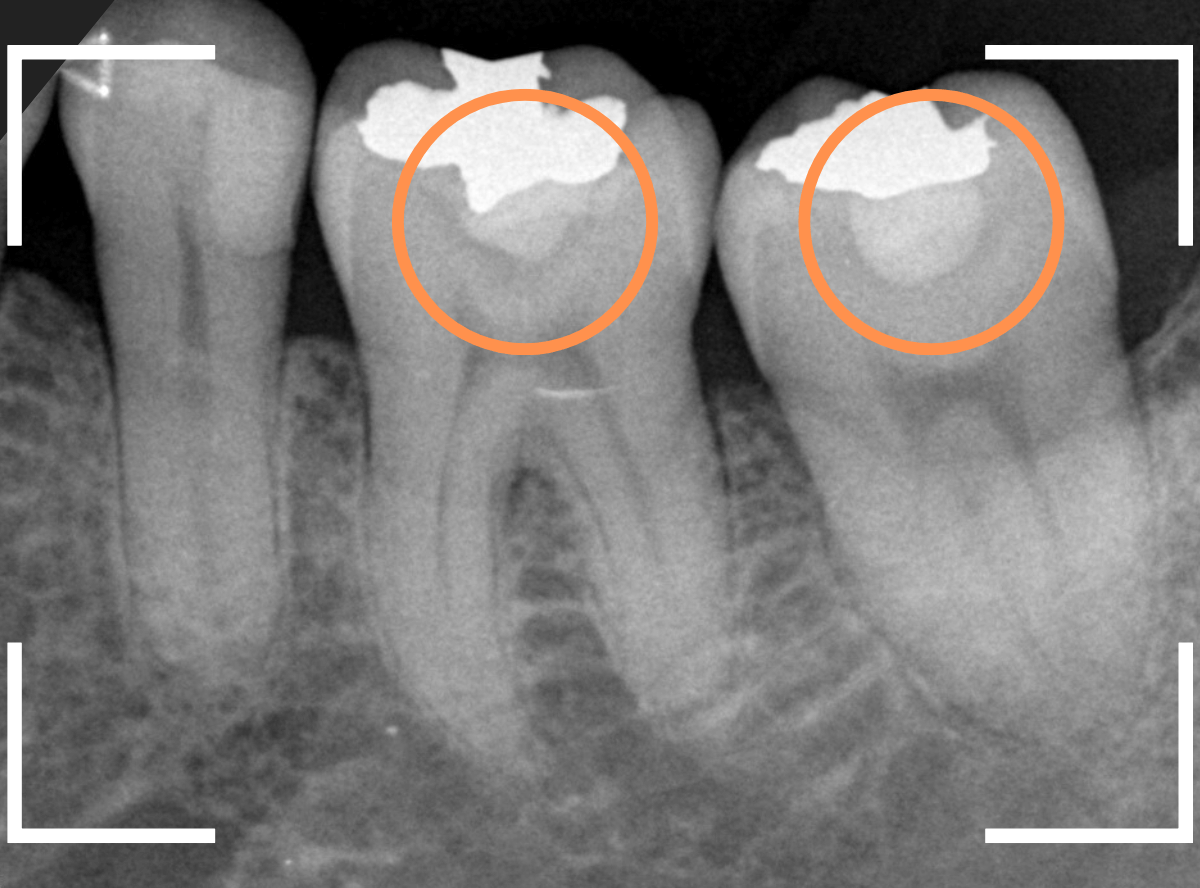

Case.1 隣り合った2本が大きな虫歯

「下の歯の奥から2番目の歯が痛む」という患者さんです。

お口の中を拝見すると、何だか1番奥の歯も怪しそうなので、歯を叩いて症状を確認してみます(打診)。

やっぱり奥から2番目の歯が痛むけど、1番奥の歯も少し痛むそうです。

レントゲン写真で確認してみました。

やはりどちらの歯も大きな虫歯でした。

2番目の歯が痛みの原因なのかもしれませんが、1番奥の歯の可能性も大いにあります。

両方の歯が原因かもしれません。

いずれにせよ、両歯とも痛みを神経に近い虫歯ですので、神経が炎症を起こして本格的な痛みになる前に治療をして神経の治療(抜髄)にならない可能性を少しでも上げたいところです。

通常であれば、初診時に大きな虫歯治療を2本行う時間的な余裕もありませんので、患者さんに事情を説明して後日治療になるのですが、今回は、予約時間よりも余裕をもって早めに来院していただいた患者さんだったので、何とか当日治療まで進める事ができました♪

まずは、麻酔をしてつめ物を慎重に外してみます。

両歯とも、色々嫌な予感のする所見です。

虫歯を可視化する、「う蝕検知液」で染め出ししてみます。

赤く染まっている場所が虫歯で、濃く染まっているところほど、虫歯は深いです。

手前の歯は一部神経が見えそうなところまで虫歯が来ていました(●部)。

患者さんのおっしゃるように、この歯が痛みの原因だったのかもしれません。

後ろの歯も、幸い神経は見えていませんが、かなり広く深い虫歯で心配な状況です。

急いで、神経を保護する薬を入れた後に、セメントで蓋をして経過観察します。

ほとんどの方はこれで何とかなりますが、痛みが出てしまい、神経の治療が必要になる方もいます。

神経の治療をすると歯の寿命は短くなってしまうので、できるだけ避けたいところです。

慎重に経過観察します。